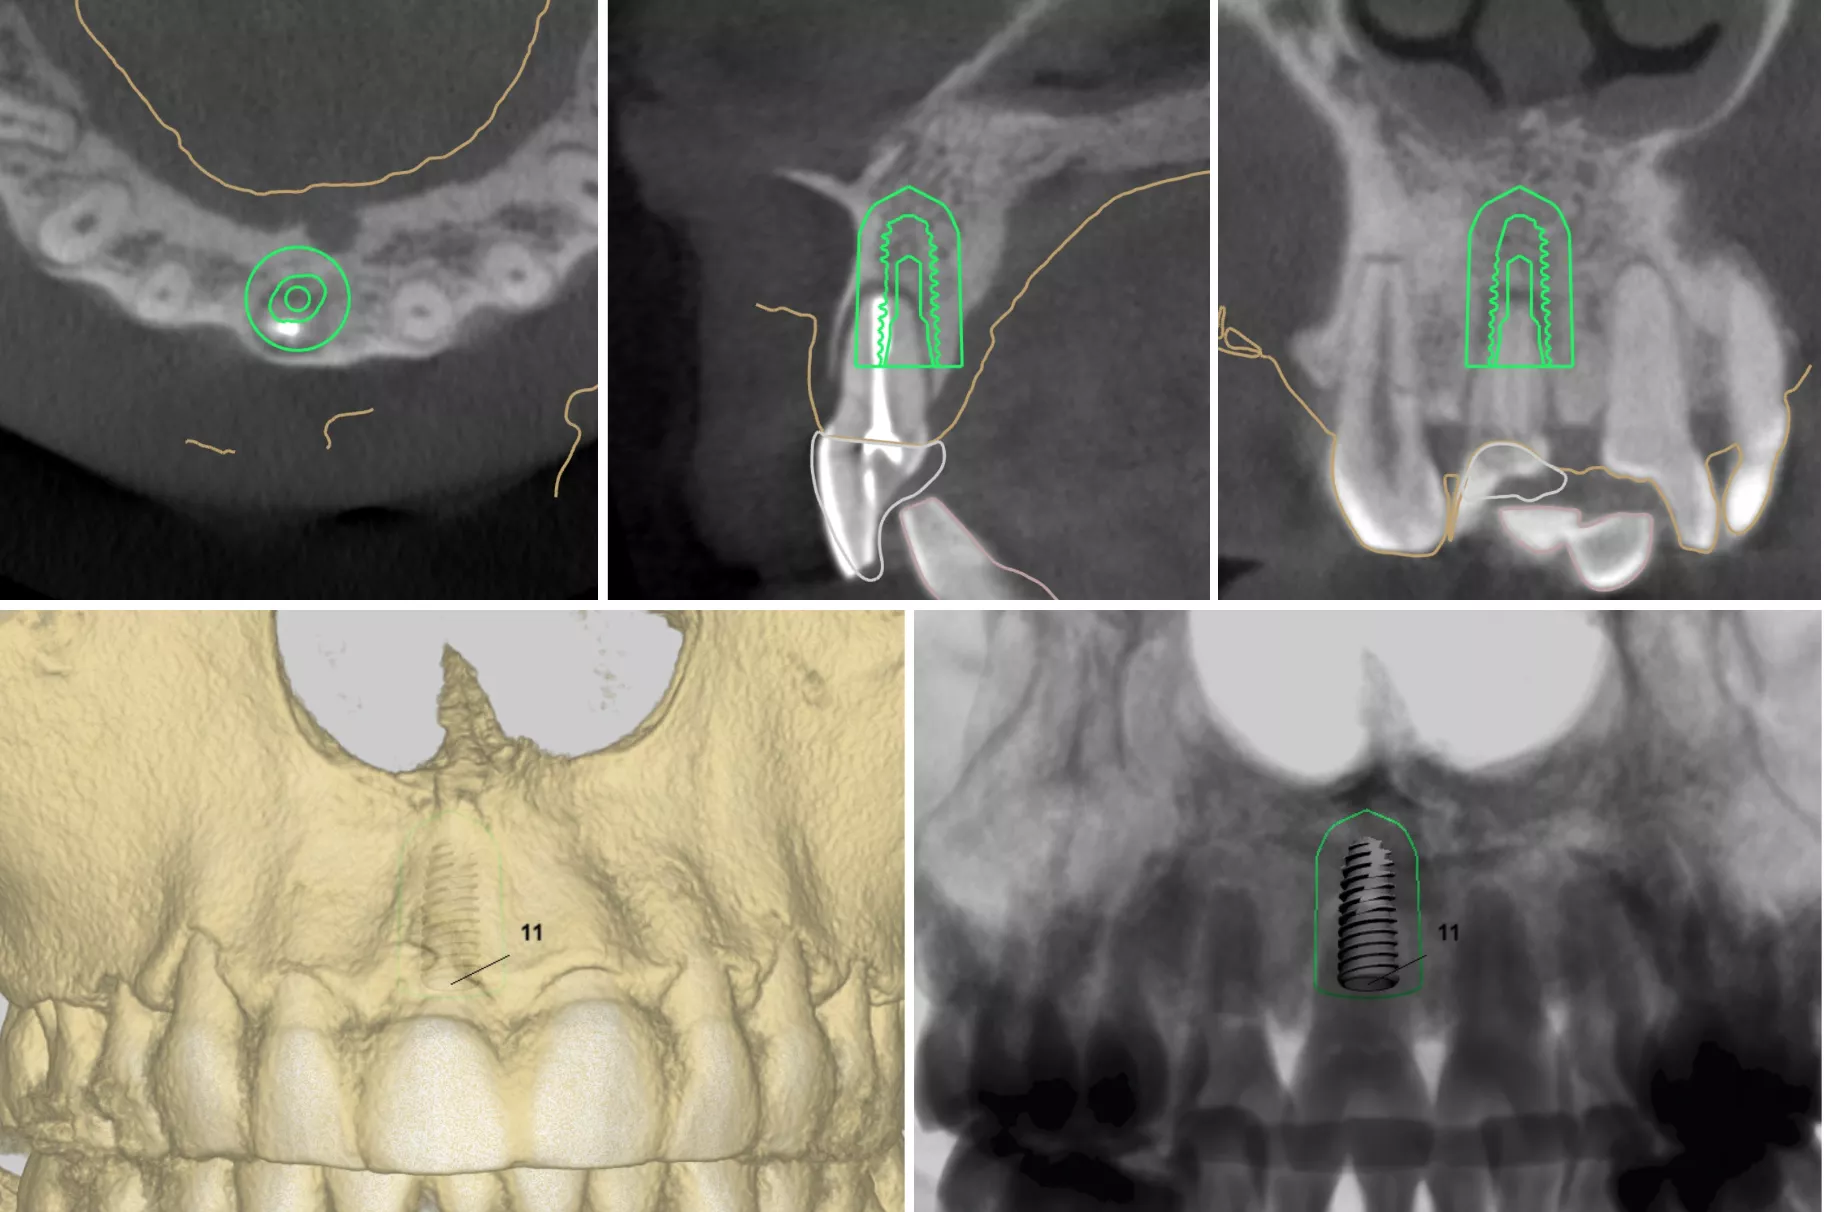

当院には、精密なインプラント治療には欠かせない歯科用CTを導入しております。さらに、インプラント専用のオペ室も完備し、大学病院レベルの環境で手術を受けることが可能です。

デジタルサージカルガイド

50,000円(税抜)